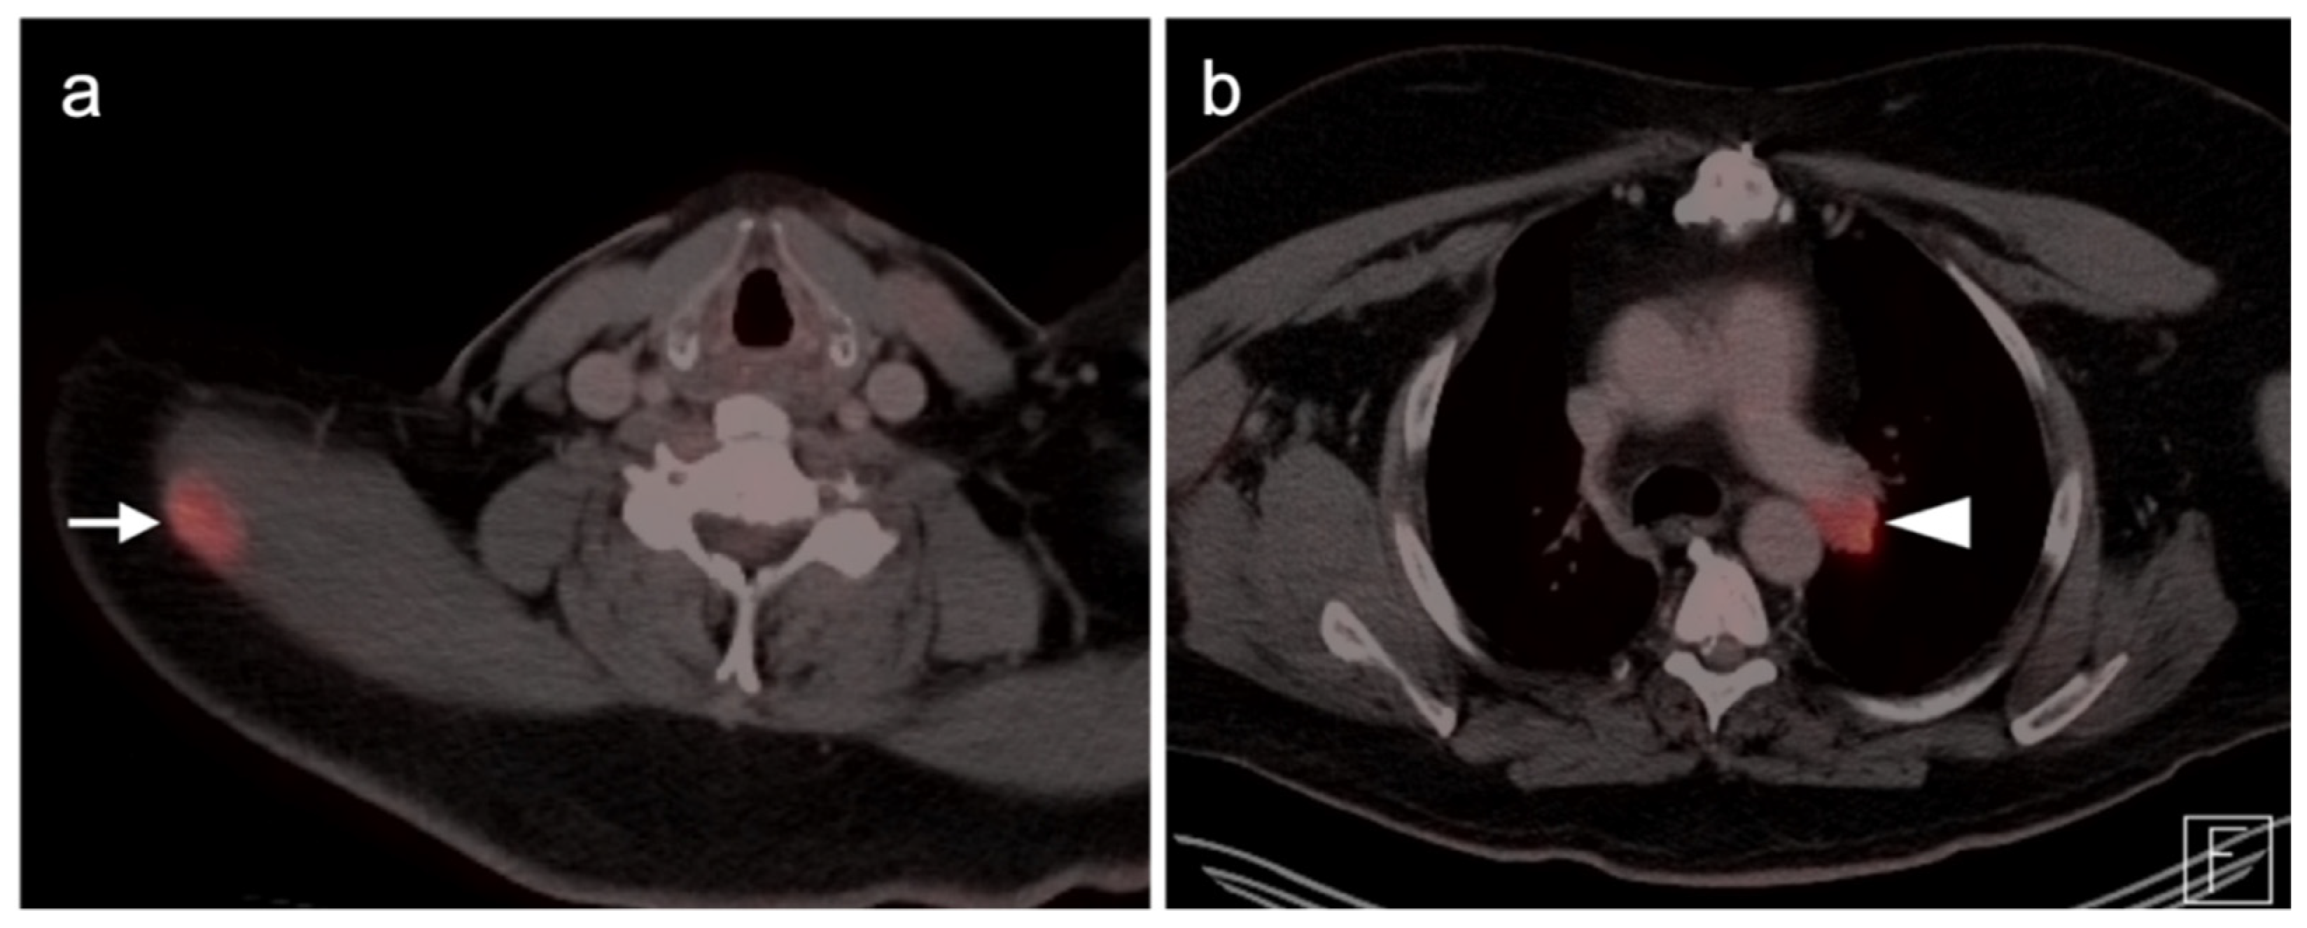

2.4. Merkel Cell Carcinoma